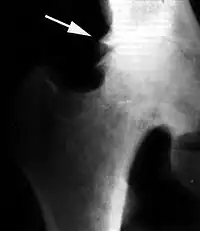

Краевые разрастания (остеофиты) при коксартрозе

Ранним рентгенологическим симптомом являются краевые костные разрастания — остеофиты — следствие активной пролиферации периферических отделов суставного хряща. Они проявляются вначале заострением краёв суставных поверхностей, а затем, нарастая, образуют массивные костные шипы и губы. Краевые остеофиты, как правило, раньше обнаруживаются со стороны суставных впадин.

Сужение суставной щели свидетельствует о значительных изменениях суставных хрящей. Суставная щель может стать клиновидной, суживаясь с одной стороны и нередко расширяясь при этом с противоположной, что указывает на недостаточность связочного аппарата и нестабильность сустава.

При остеоартрозе утрачивается амортизационная функция суставных хрящей, предохраняющих костную ткань от механических перегрузок. Как компенсация развивается остеосклероз субхондральной губчатой кости. Особенно он выражен при коксартрозе в крыше вертлужной впадины, распространяясь иногда почти на всё тело подвздошной кости. Однако рано или поздно этот механизм компенсации становится недостаточным. Механические силы, передающиеся непосредственно с одной суставной поверхности на другую, вызывают атрофию от давления их наиболее нагружаемых участков и прежде всего центральных отделов суставных головок. Вследствие этого они уплощаются и одновременно расширяются.